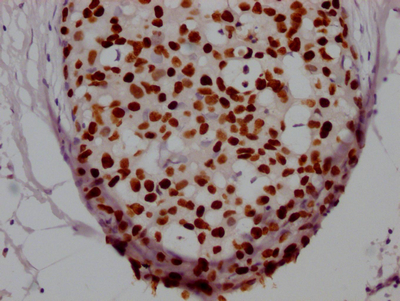

IHC image of CSB-RA246102A0HU diluted at 1:100 and staining in paraffin-embedded human prostate tissue performed on a Leica BondTM system. After dewaxing and hydration, antigen retrieval was mediated by high pressure in a citrate buffer (pH 6.0). Section was blocked with 10% normal goat serum 30min at RT. Then primary antibody (1% BSA) was incubated at 4℃ overnight. The primary is detected by a Goat anti-rabbit IgG polymer labeled by HRP and visualized using 0.05% DAB.